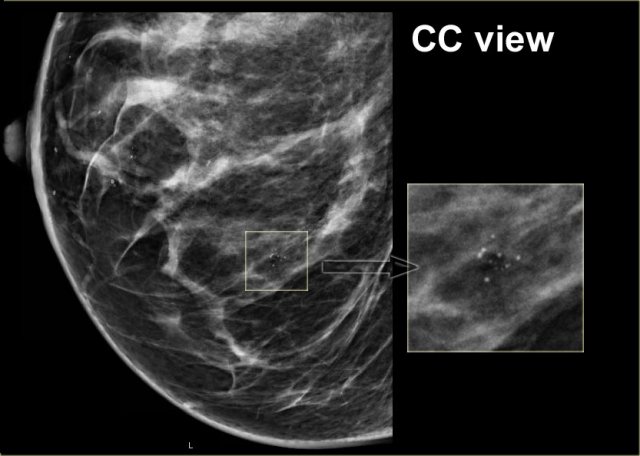

Click to enlarge Click to enlarge

Here another example of the tatoo-sign.

First notice that there are some calcifications that are clearly located within the skin (arrows).

The cluster calcifications on the MLO-view has the exact configuration as the cluster on the CC-view (next image).

On the CC-view the configuration of the microcalcifications is exactly the same.

If these calcifications were located in the centre of the breast they should have a different configuration, because the projection is different.

Only when calcifications are located within the skin their configuration stays the same.